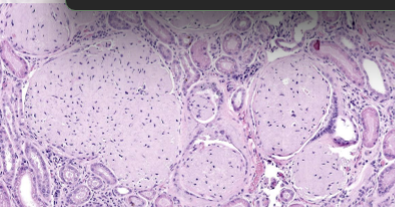

What is hyperplasia, what caused this, what is the mechanism?

increase in no of cells, only in cells that can divide. increased mitotic activity.

cells proliferate in response to hormones / growth factors

can be caues by inflammation, physical trauma

give examples of hormonal hyperplasia and compensatory hypoplasia

hormonal -

eg proliferation or mammary and uterine epithelium during pregnancy

compensatory -

with partial loss of parenchyma

in symmetrical organs with functional loss of one organ.

List three triggers for pathological hyperplasia

excessive hormone production or effect of growth factors, eg cystic endometrial hyperplasia

attempt of regeneration, eg nodular hyperplasia in spleen, liver, pancreas

with viral infections eg papilloma